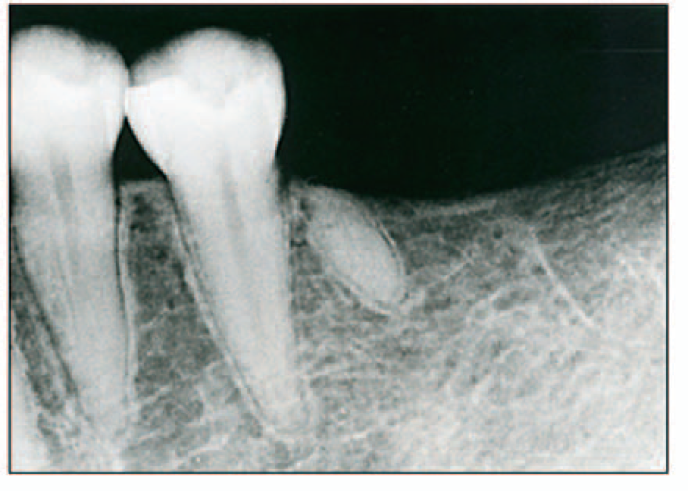

Root tip